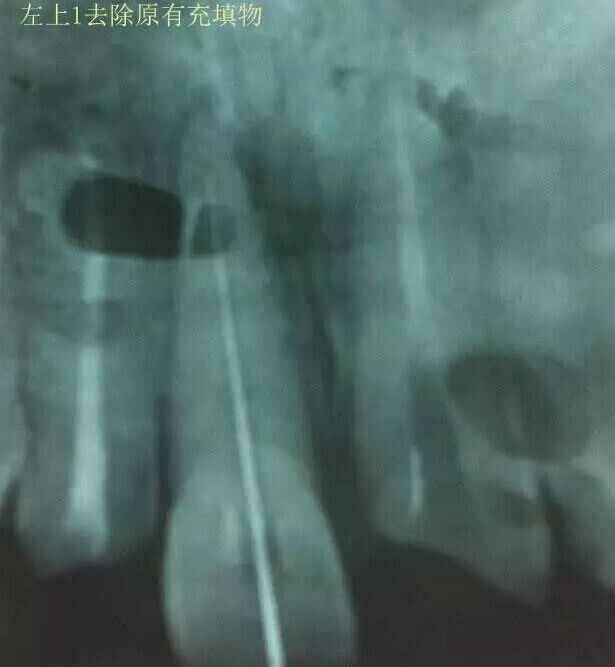

1,11 21去除根充物。

治療過程:經(jīng)患者同意。H銼去除11 21原有充填物,未發(fā)現(xiàn)明顯滲出物,無異味。K銼疏通根管,VDW根測儀測量長度,11牙20mmWL,21牙20mmWL。S3鎳鈦器械預(yù)備根管。(全程1%次氯酸鈉沖洗EDTA溶解潤滑)試尖片顯示牙膠未到位,繼續(xù)向牙根尖各2mm進入預(yù)備。吸潮紙尖吸干根管,登士柏樹脂根充糊劑輸送至根尖部位,以測量數(shù)據(jù)用牙膠尖冷充側(cè)壓充填根管,3M玻璃離子封閉根管口。不可用患牙啃咬硬物,擇日冠修復(fù)。

輔助檢查:插針X線片顯示根管內(nèi)充填物已經(jīng)取出。試尖片顯示牙膠尖未到位,繼續(xù)用K銼和機括向根尖預(yù)備。根充結(jié)束片顯示根充密實,無超充,無欠充。